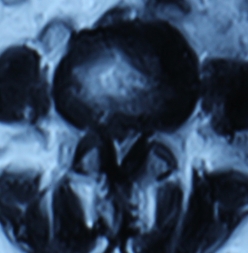

2. 患者董某,女,70岁,因“腰部疼痛并右下肢疼痛、麻木1年余,加重10天”入院。入院前曾多次行针灸、理疗、骶管封闭等治疗,经治疗后病情复发。入院见患者腰痛并右下肢疼痛,双足麻木,间歇性跛行,跛行距离约50米。查:直腿抬高试验右30°阳性,右踇背伸肌力、腓骨长短肌肌力Ⅲ级,双小腿外侧、足背皮肤感觉减退,右侧为甚。入院后诊断为腰椎间盘突出症。患者既往患高血压、冠心病、慢性胆囊炎、胆结石病史,形体肥胖。入院后完善检查,明确诊断,请相关科室会诊后认为手术风险大且患者形体肥胖,为手术增加难度,势必延长手术时间,增加手术风险。经科室讨论后行经皮椎间孔镜下髓核摘除,手术麻醉方式为局麻。入院后第三日手术,经椎间孔入路椎间孔镜下髓核摘除椎管扩大成形术。手术顺利,术中无出血,手术时间约1小时。术中可与患者交流。术后患者即可感右下肢无疼痛,第二天佩戴腰围下地活动后双下肢无不适。术后第三天出院,术后第三天复查腰椎MRI示突出髓核已摘除,神经根无受压。术后随访三月,患者目前病情恢复良好,无下肢疼痛。

术前患者腰椎MRI